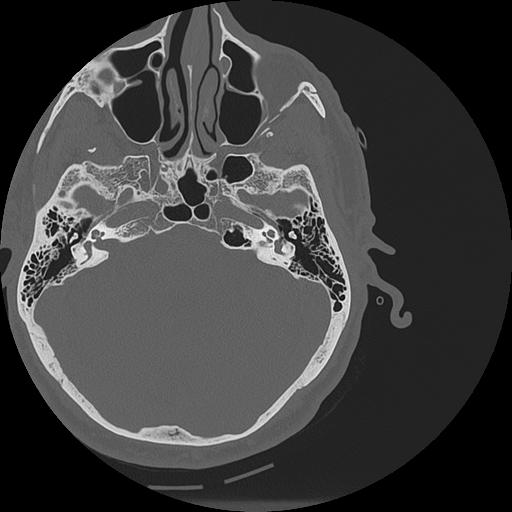

7 HUESO,,Vol,0.5,HUESO,,